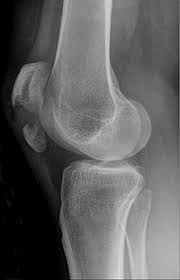

Löcher im knochen nach metallentfernung. Die ist hart und sehr spitz und lässt sich nicht bewegen. Obwohl ein Schraubenloch noch lange im Röntgenbild nachweisbar ist kommt es zu einer fortschreitenden Geflechtknochenbildung die die Stresskonzentration im Schraubenloch zunehmend herabsetzt. Bei Knie-OPs wird die Metallentfernung in der Regel cirka nach einem Jahr durchgeführt.

Obwohl sehr selten kann es im Rahmen der Metallentfernung ua. Nein dies ist ein völlig normaler Befund.

Gelegentlich ist es nicht möglich das Material vollständig zu entfernen so dass es auch vorkommen kann dass Reste des Metalls im Körper belassen werden müssen. Ich habe neulich das Gleiche bei einem Schrank erlebt. Die Stabilität sollte nach der Entfernung kein Problem sein weil die Schrauben und Nägel immer versetzt angeordet sind also die Löcher nie über- untereinander lägen. Die ist hart und sehr spitz und lässt sich nicht bewegen. Sollten Metallteile weggebrochen sein werden die dann auch im Knochen belassen die tun nix. Hier ist die Radiusfraktur nicht mit einer Platte sondern mit Kirschnerdrähten erfolgt. Obwohl ein Schraubenloch noch lange im Röntgenbild nachweisbar ist kommt es zu einer fortschreitenden Geflechtknochenbildung die die Stresskonzentration im Schraubenloch zunehmend herabsetzt. Hierbei wird in manchen Fällen lediglich die einzelne Stellschraube entfernt wobei die komplette Metallentfernung ungefähr nach einem Jahr beginnt. Auch nach einem Jahr kann man im Röntgenbild nach einer Schraubenentfernung die Schraubenkanäle gut erkennen.